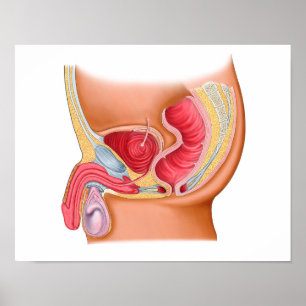

Medicinsk illustration av en Rectourethral Fistula Hälsningskort

Försäljningspris 49,00 kr. Ursprungligt pris 54,00 kr.

Hondjurens urinvägssystem, märkt poster

Pris705,00 kr